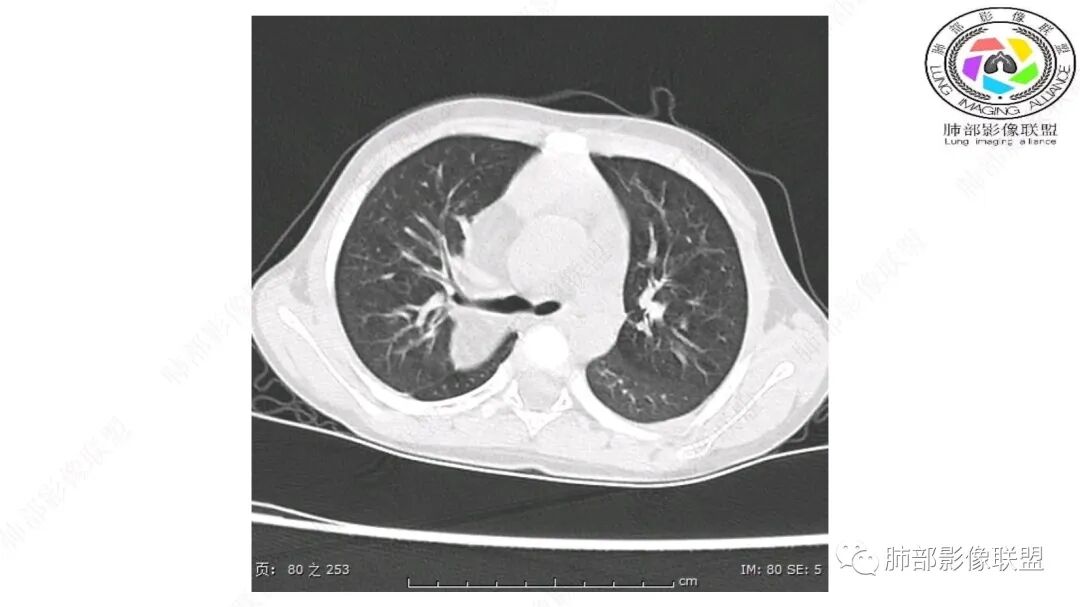

患儿3岁 咳嗽检查发现纵隔占位。右肺上叶受压表现,占位以脂肪组织密度为主,似见分隔,首先考虑为脂肪母细胞瘤,鉴别脂肪瘤,畸胎瘤。

第一个问题:定位:肺内?纵隔?

病灶属于交界区,主体位于肺内,占位效应明显,前方突入胸壁,胸腺受压变形,胸膜显示欠清楚;病灶包绕上叶肺动脉;似乎有体动脉供血。符合肺内的点:包绕上叶肺动脉分支;符合纵隔的点:前方似乎突入胸壁,与胸腺关系比较密切,但是与上腔静脉的关系提示病灶不支持纵隔来源,前纵隔的常规会将上腔静脉受压后移、外移,这是不符合的。

从这个角度符合肺内的,有一点不太踏实的是:似乎突入前胸壁。

2.肺动脉穿行也许是肺内来源最重要支持点!